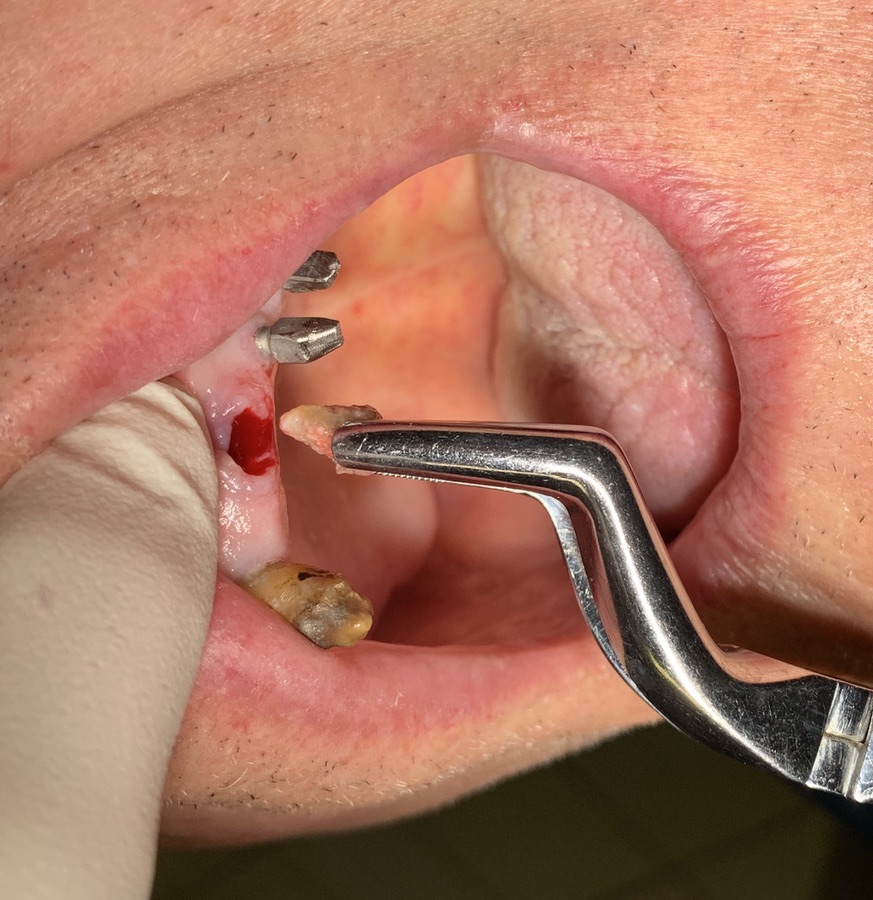

Tipo di impianto: Tramonte     Numero di impianti inseriti: 2     Saldatura: No    Zona dentale: 21   23

App.Rx Endorale:Vix Win     Tac: No     Situazione estrattiva:  impianti postestrattivi immediati   Densità Secondo Misch: D2

Operatore 1:  Dr. Bellini    Operatore 2: Dr. Bazzoli     Sequenza frese: Solo fresa lanceolata    Sequenza maschiatori: solo diametro 4 mm.

D- rendono inutile lo scollamento,

E- riducono il consumo di osso quasi a zero, per la perforazione e l’inserimento,